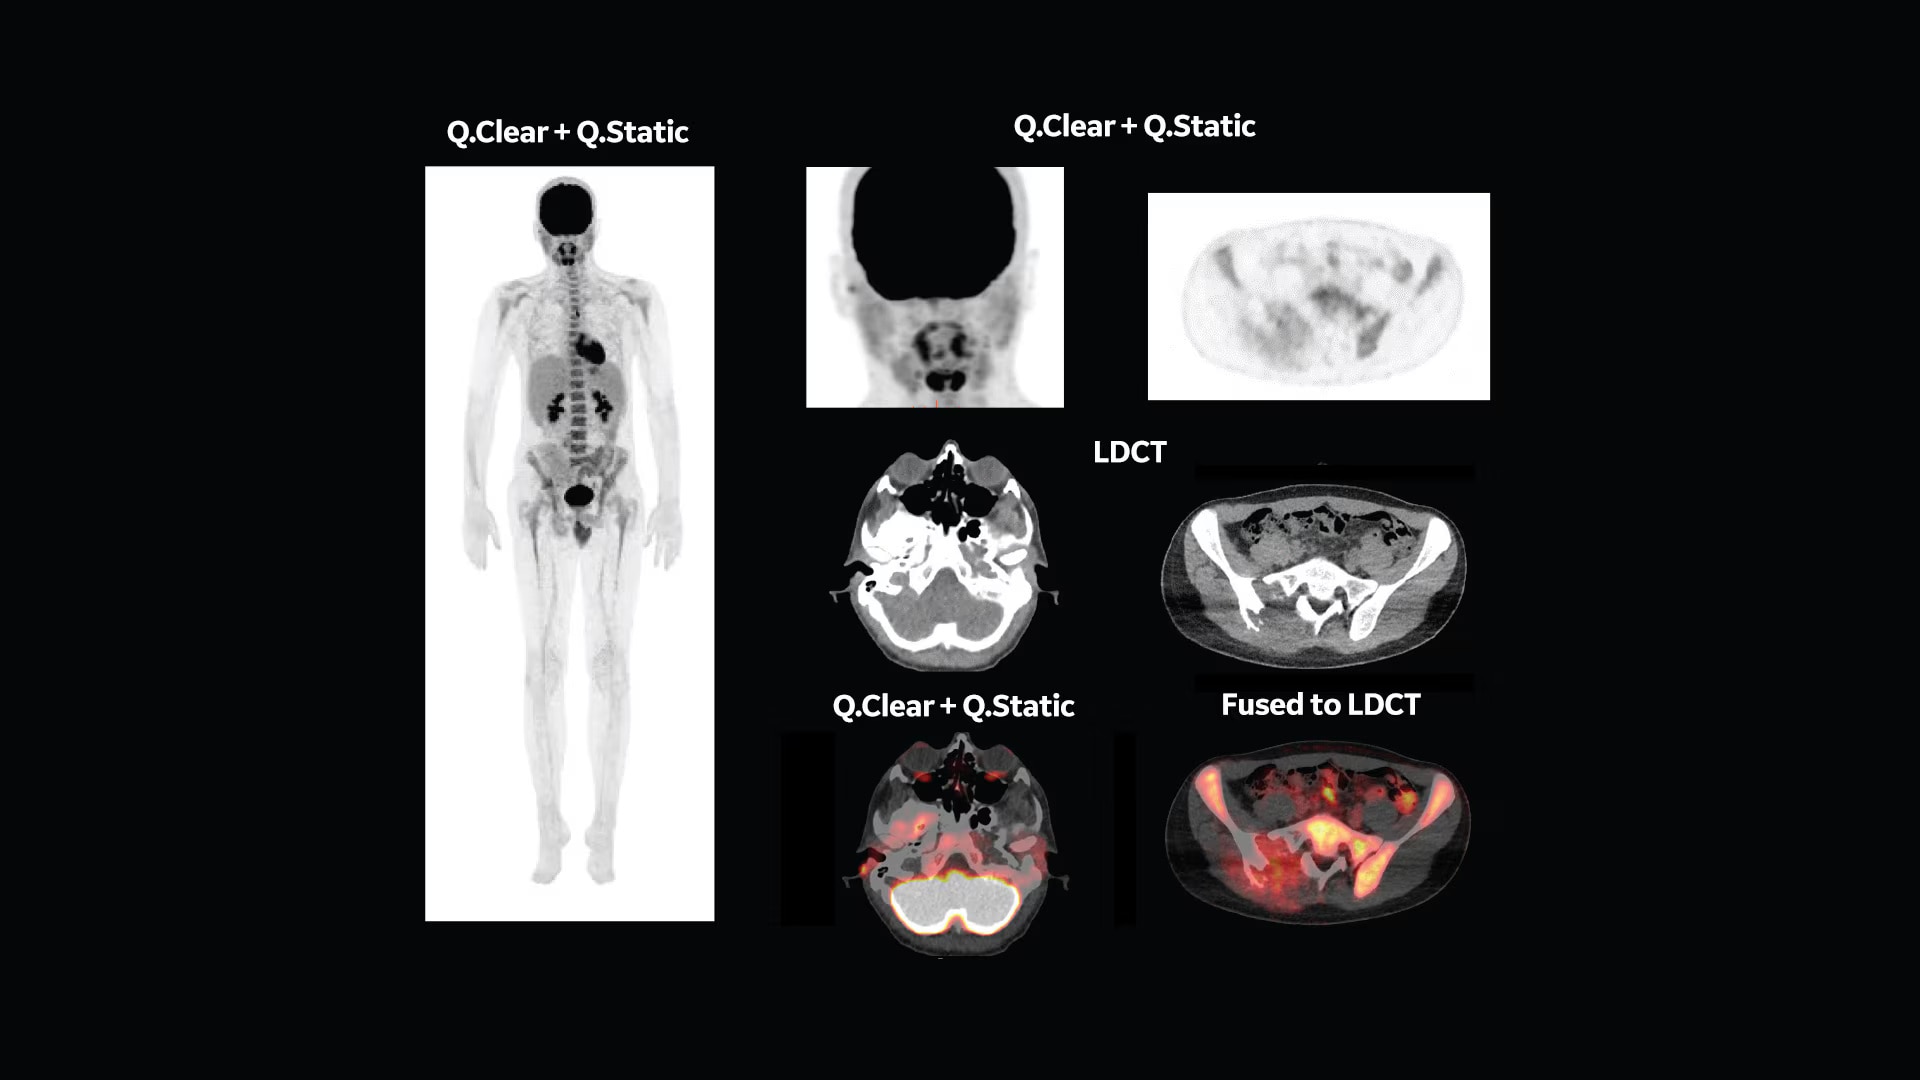

Q.Clear (BSREM): accurate data points to trusted treatment

Since its introduction, Q.Clear has delivered fast and efficient quantitation readings for confident diagnosis and precise treatment response assessment. Up to a 2x improvement in quantitative SUV (SUVmean). Up to a 2x improvement in image quality (SNR).